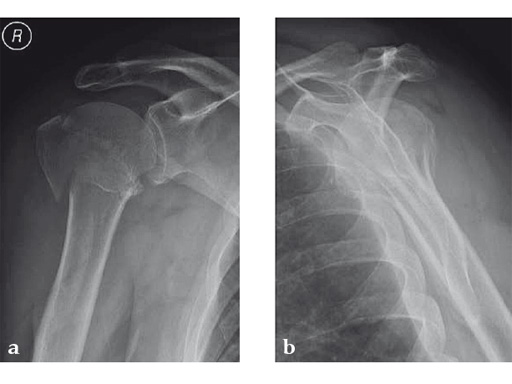

Case 1: A three-part valgus impacted fracture of the proximal humerus in a 47-year-old woman.

Case 2: Three-part valgus displaced fracture of the proximal humerus in a 63-year-old man.